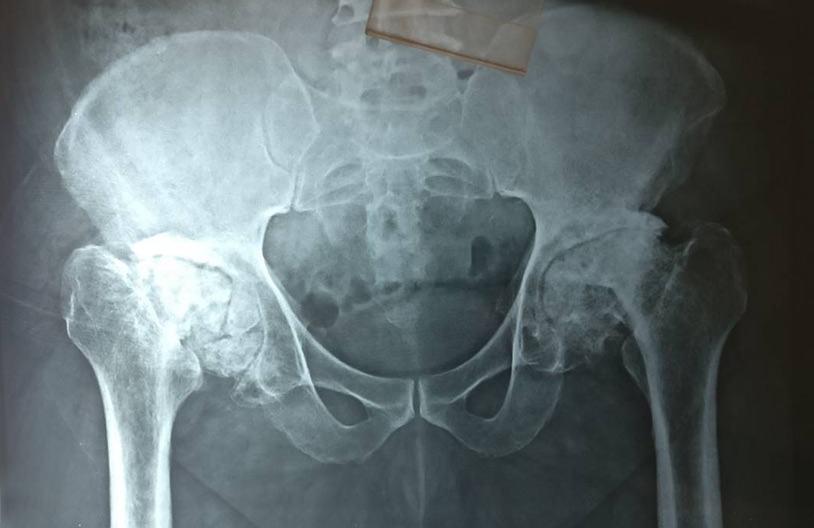

A 55 yrs old male from Dewas suffering for last 10 years from bilateral hip Avascular necrosis, not able to walk at all underwent bilateral total hip replacement (THR) at our centre using latest techniques giving best result to the patient. He started walking the next day. It was a life changing experience for the patient from not able to walk all to walking painlessly.

We are treating hip avascular necrosis and other complex hip disorders on regular basis in central India, Indore. Procedure done by our dedicated Joint Replacement Surgeon Dr Sachin Chhabra from Push Orthopaedic Centre.